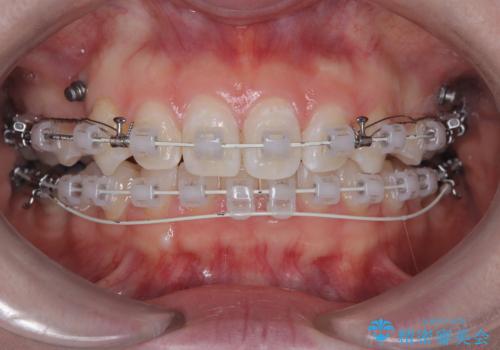

- 右上の八重歯と歯のデコボコ、そして上下の歯の中心(正中)のズレを気にされて来院されました。精密な検査の結果、歯が並ぶスペースが不足しているため、上顎の小臼歯(前から数えて4番目の歯)を抜歯し、そのスペースを利用して歯並び全体を整える治療計画を立案しました。これにより、八重歯の位置を適切に改善し、叢生(歯のデコボコ)を解消するとともに、上下の正中線のズレも改善することを目指します。

今回の矯正治療では、歯が並ぶスペースを確保するため、上顎の小臼歯を抜歯しました。抜歯によってできたスペースを有効活用し、ワイヤーやブラケットを使って右上の八重歯を適切な位置へ移動させ、叢生を解消していきました。また、治療を通じて上下の歯の中心である正中線のズレも改善するよう、慎重に歯を動かしました。治療の結果、長年気にされていた八重歯と歯のデコボコが解消され、上下の正中線も一致。機能的にも審美的にもバランスの取れた、美しい歯並びと笑顔を獲得していただけました。